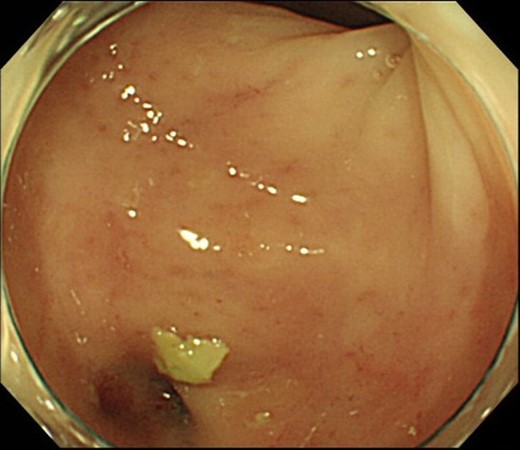

Case 1 was a 71-year-old man with a BMI of 29.7 kg/m2. Laparoscopic low anterior resection (LAR) and ileostomy was performed for rectal cancer in 2017 years. Postoperative fever and lower abdominal pain were noted, and colonoscopy was performed, and anastomotic leakage was noted with a correction of about 1/2 around the 6 o’clock direction of the anastomotic region, and fistula and formation of a large abscess cavity. After identification (Fig. 1), a tube was inserted for drainage and conservative treatment was performed. The patient was discharged on POD 46. Four months after the operation, marked improvement in the abscess cavity was noted but still remained (Fig. 2a and b). Anastomotic leakage was almost improved by colonoscopy at 17 months after surgery, but at the preference of the patient we performed colostomy 22 months after surgery (Fig. 3). It took a long time to improve intestinal movement of the colon because the large intestinal tract had not been used for a long time, and conservative treatment was performed using a nasogastric tube for paralytic ileus. Diet was initiated 7 days after surgery, and the patient was discharged from the hospital 14 days after surgery. The Wexner score [2] was 19 points one month after closure, 17 points 3 months after the operation and 16 points after 6 months after the operation, and severe anal dysfunction was observed, but gradually improved.

Colonoscopy shows that the suture failure has improved with only a slight depression.